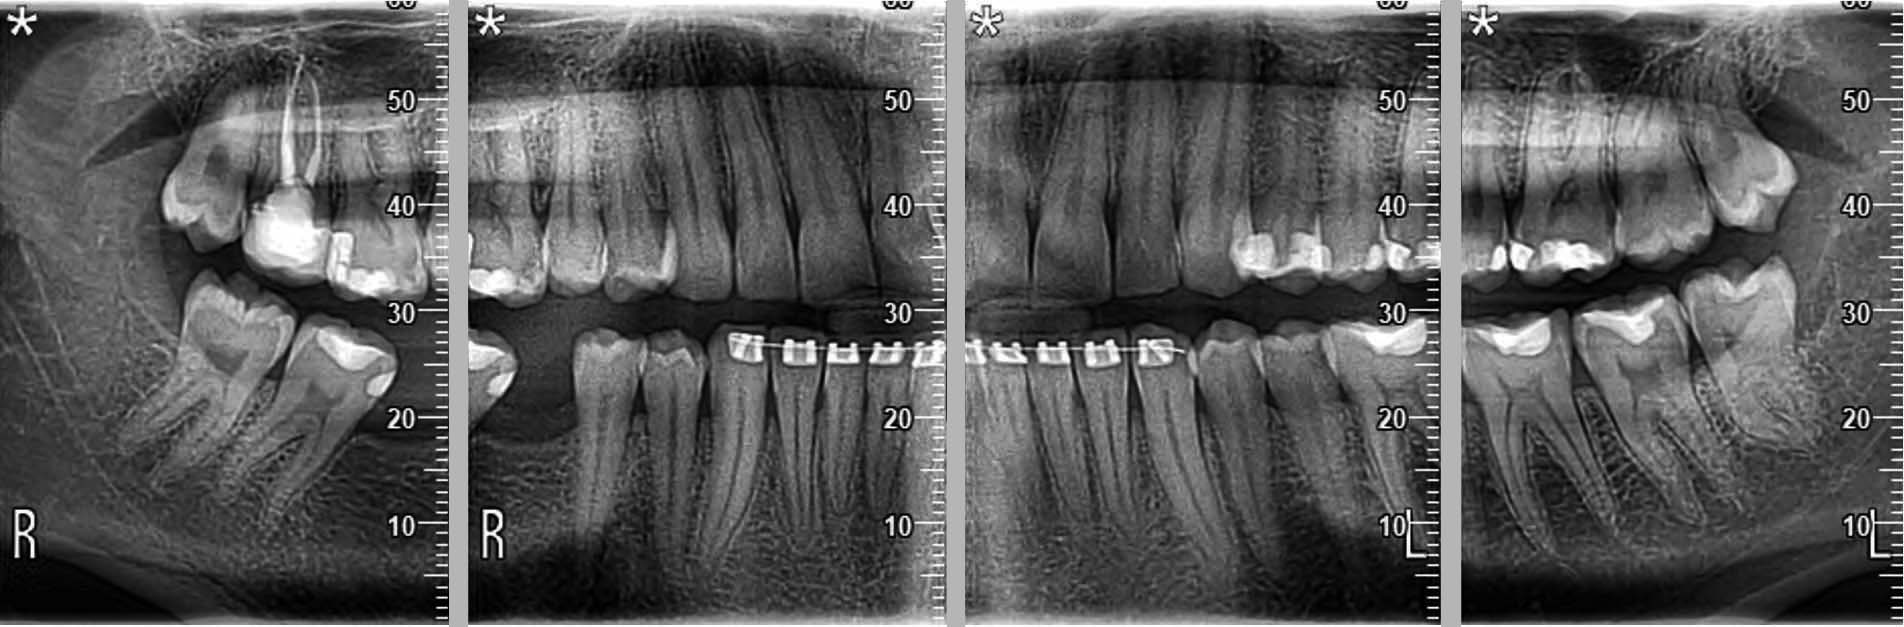

Yeni nesil hassas Cmos Flat Panel Teknolojisi. Görüntü kesitleri eskiye göre 2 kat daha keskin ve net görüntü almayı sağlamaktadır. Panoramik görüntülemede devrim yaratan Panoral 5 MultiPan çekim tekniği ile tek panoramik doz ile 5 ayrı katmanda görüntü alınır. Reel 16 bit yüksek gri skalası ile yüksek çözünürlük ve kesin tanı imkânı sunmaktadır. PANORAL 5 MULTIPAN Panoramik Röntgen Çekim Tekniği: CMOS Flat Panel Hassas Sensör teknolojisi tek bir panoramik doz ile horizontal düzlemde 3 mm. aralıkla, hastanın 5 ayrı vertikal panoramik görüntüsünün elde edilmesini sağlamaktadır. Bu şekilde net alan derinliğine girmeyen bir diş var ise bir önceki veya bir sonraki filmde görülebilir. Panoral 5 MULTIPAN görüntüleme tekniği; maloklüzyon ve hasta pozisyonlandırma hataları nedeniyle oluşabilecek görüntü bozukluklarını elemine edebilmektedir. Böylelikle panoramik röntgen çekimlerinde pozisyonlandırma hatalarına bağlı çekim tekrarlarına da gerek kalmaz.

• Maksimum çözünürlük ve ortogonalite • Sabit büyütme • Ark segmentasyonu